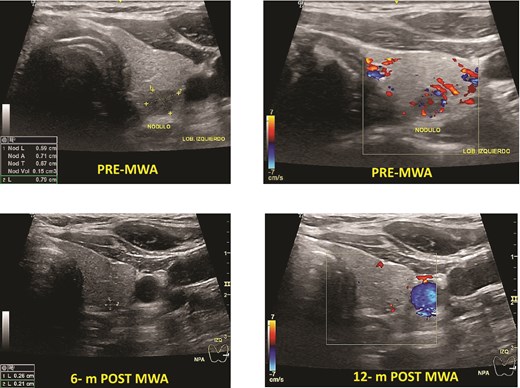

Benign thyroid nodules pre- and post-MWA (3, 6, and 12 months), see the changes in volume and the ultrasound aspect of the nodule.

Before MWA, the overall median volume was 1.54 (0.20–34.08) ml. After ablation, the 1-month, 3-month, 6-month, and 12-month median volumes were 1.80 (0.13–8.72) ml; 0.65 (0.01–12.23) ml, 0.11 (0.01–0.50) ml, and 0.05 (0.00–2.00) ml, respectively. The overall nodular volume reduced significantly after MWA treatment over time (P < .001). The VRR was 49%, 82%, 96%, and 97% at 1, 3, 6, and 12-month follow-ups, respectively (Table 3). Figure 1 shows an example of the change in volume of each patient’s nodule volume over time. The mean TSH in the 1-month follow-up was 2.84 (SD 1.61).